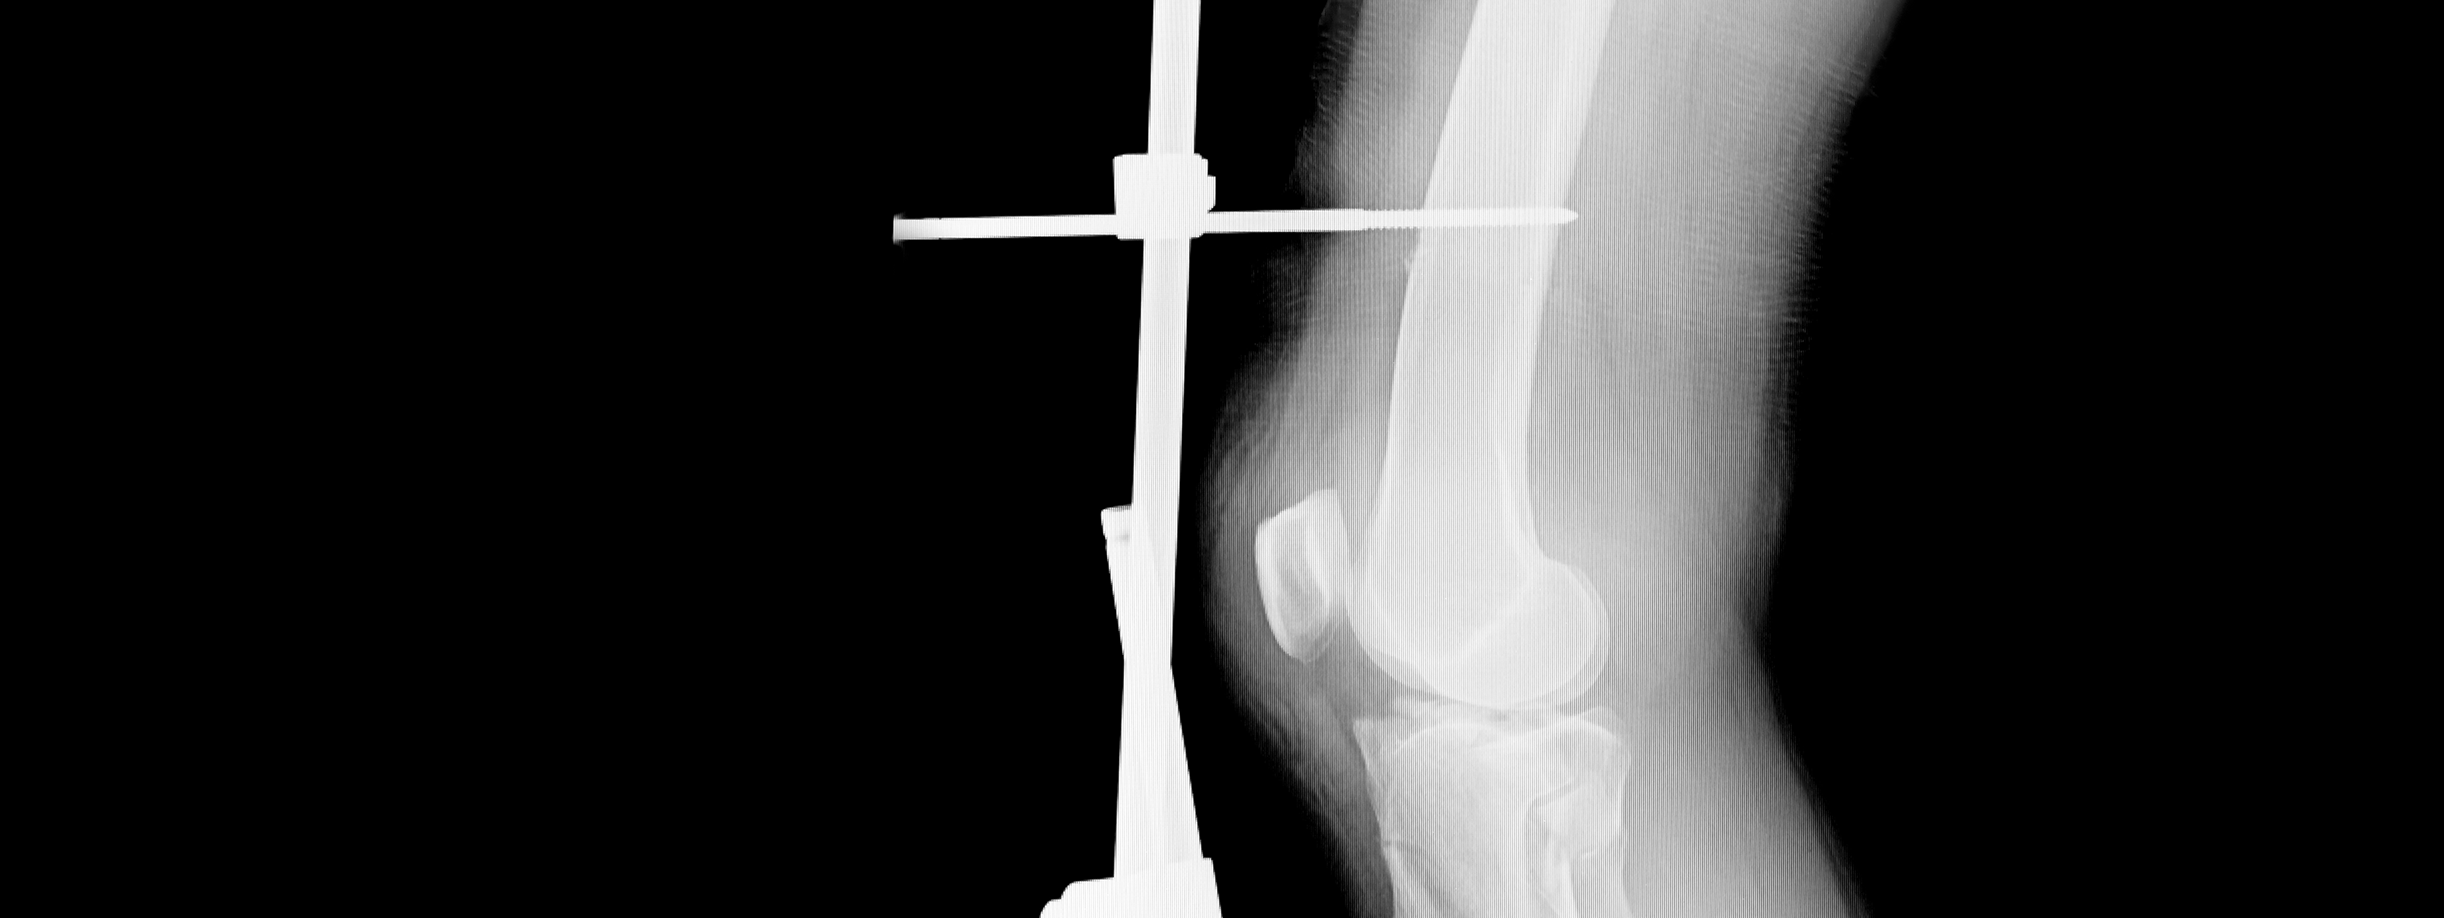

Fijadores Externos

Los fijadores externos son estructuras que se utilizan para estabilizar huesos rotos mediante una serie de barras, alambres y aros situados fuera del cuerpo. Pueden utilizarse de forma temporal o permanente